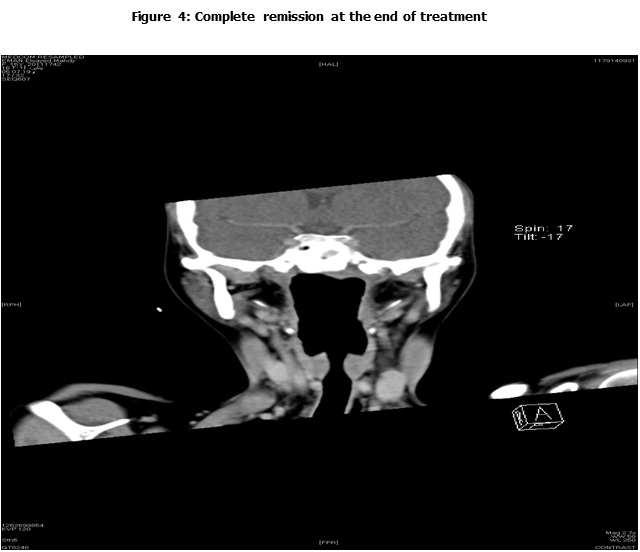

This is a retrospective study including all the newly diagnosed pediatric NPC who were diagnosed and treated at the Children Cancer Hospital Egypt (CCHE) during the period from July 2007 to December 2012. All imaging studies (e.g., CT or MRI scans) were reviewed by a senior head and neck radiologist for proper staging and assessment of tumor response. Patients were staged according to AJCC staging system. Modified version of the Response Evaluation Criteria in Solid Tumor (RECIST) was used to assess response.

This is a retrospective study including all newly diagnosed pediatric NPC at Children Cancer Hospital Egypt CCHE during the time period from July 2007 to December 2012. The patients' profiles were systematically reviewed for characteristics including pathology, laboratory, radiological work up and documented toxicities. All imaging studies (e.g., CT and MRI scans) were reviewed by a senior head and neck radiologist for proper staging and assessment of tumor response.

Pretreatment evaluation included a complete history and physical examination, complete blood count, serum biochemistry tests (including evaluation of electrolyte levels, hepatic and renal function tests), CT or MRI scans of the head and neck region, chest and bone scan. During therapy weekly examinations and laboratory evaluations were performed. Tumor response was assessed by clinical examination with appropriate MRI imaging studies after completion of neoadjuvant chemotherapy and at the end of radiotherapy.

Radiotherapy planning was performed 2-3 weeks after the third course of neoadjuvant chemotherapy. A customized thermoplastic immobilization cast was used for all patients and a CT simulation was applied using iv contrast injection and a 3 mm slice thickness. The gross tumor volumes (GTV) as well as all organs at risk were delineated. Clinical target volume was created by adding a safety margin that encompass all possible microscopic and expected tumor extensions. An isotropic expansion of 5 mm was added to form the planning target volume (PTV) according to the department policy. Intensity modulated radiotherapy (IMRT) technique using KonRad treatment planning system was applied to deliver a dose of 61.2 Gy in 37 fractions to high risk tumor and nodal areas, and 54 Gy to the low risk nodal area applying simultaneous integrated boost technique for CR and PR patients. Those who had SD received 66.6Gy in 37 fraction, while for patients with PD, they received 70.2 Gy in 39 fractions. Toxicity was recorded and graded according the WHO toxicity criteria.